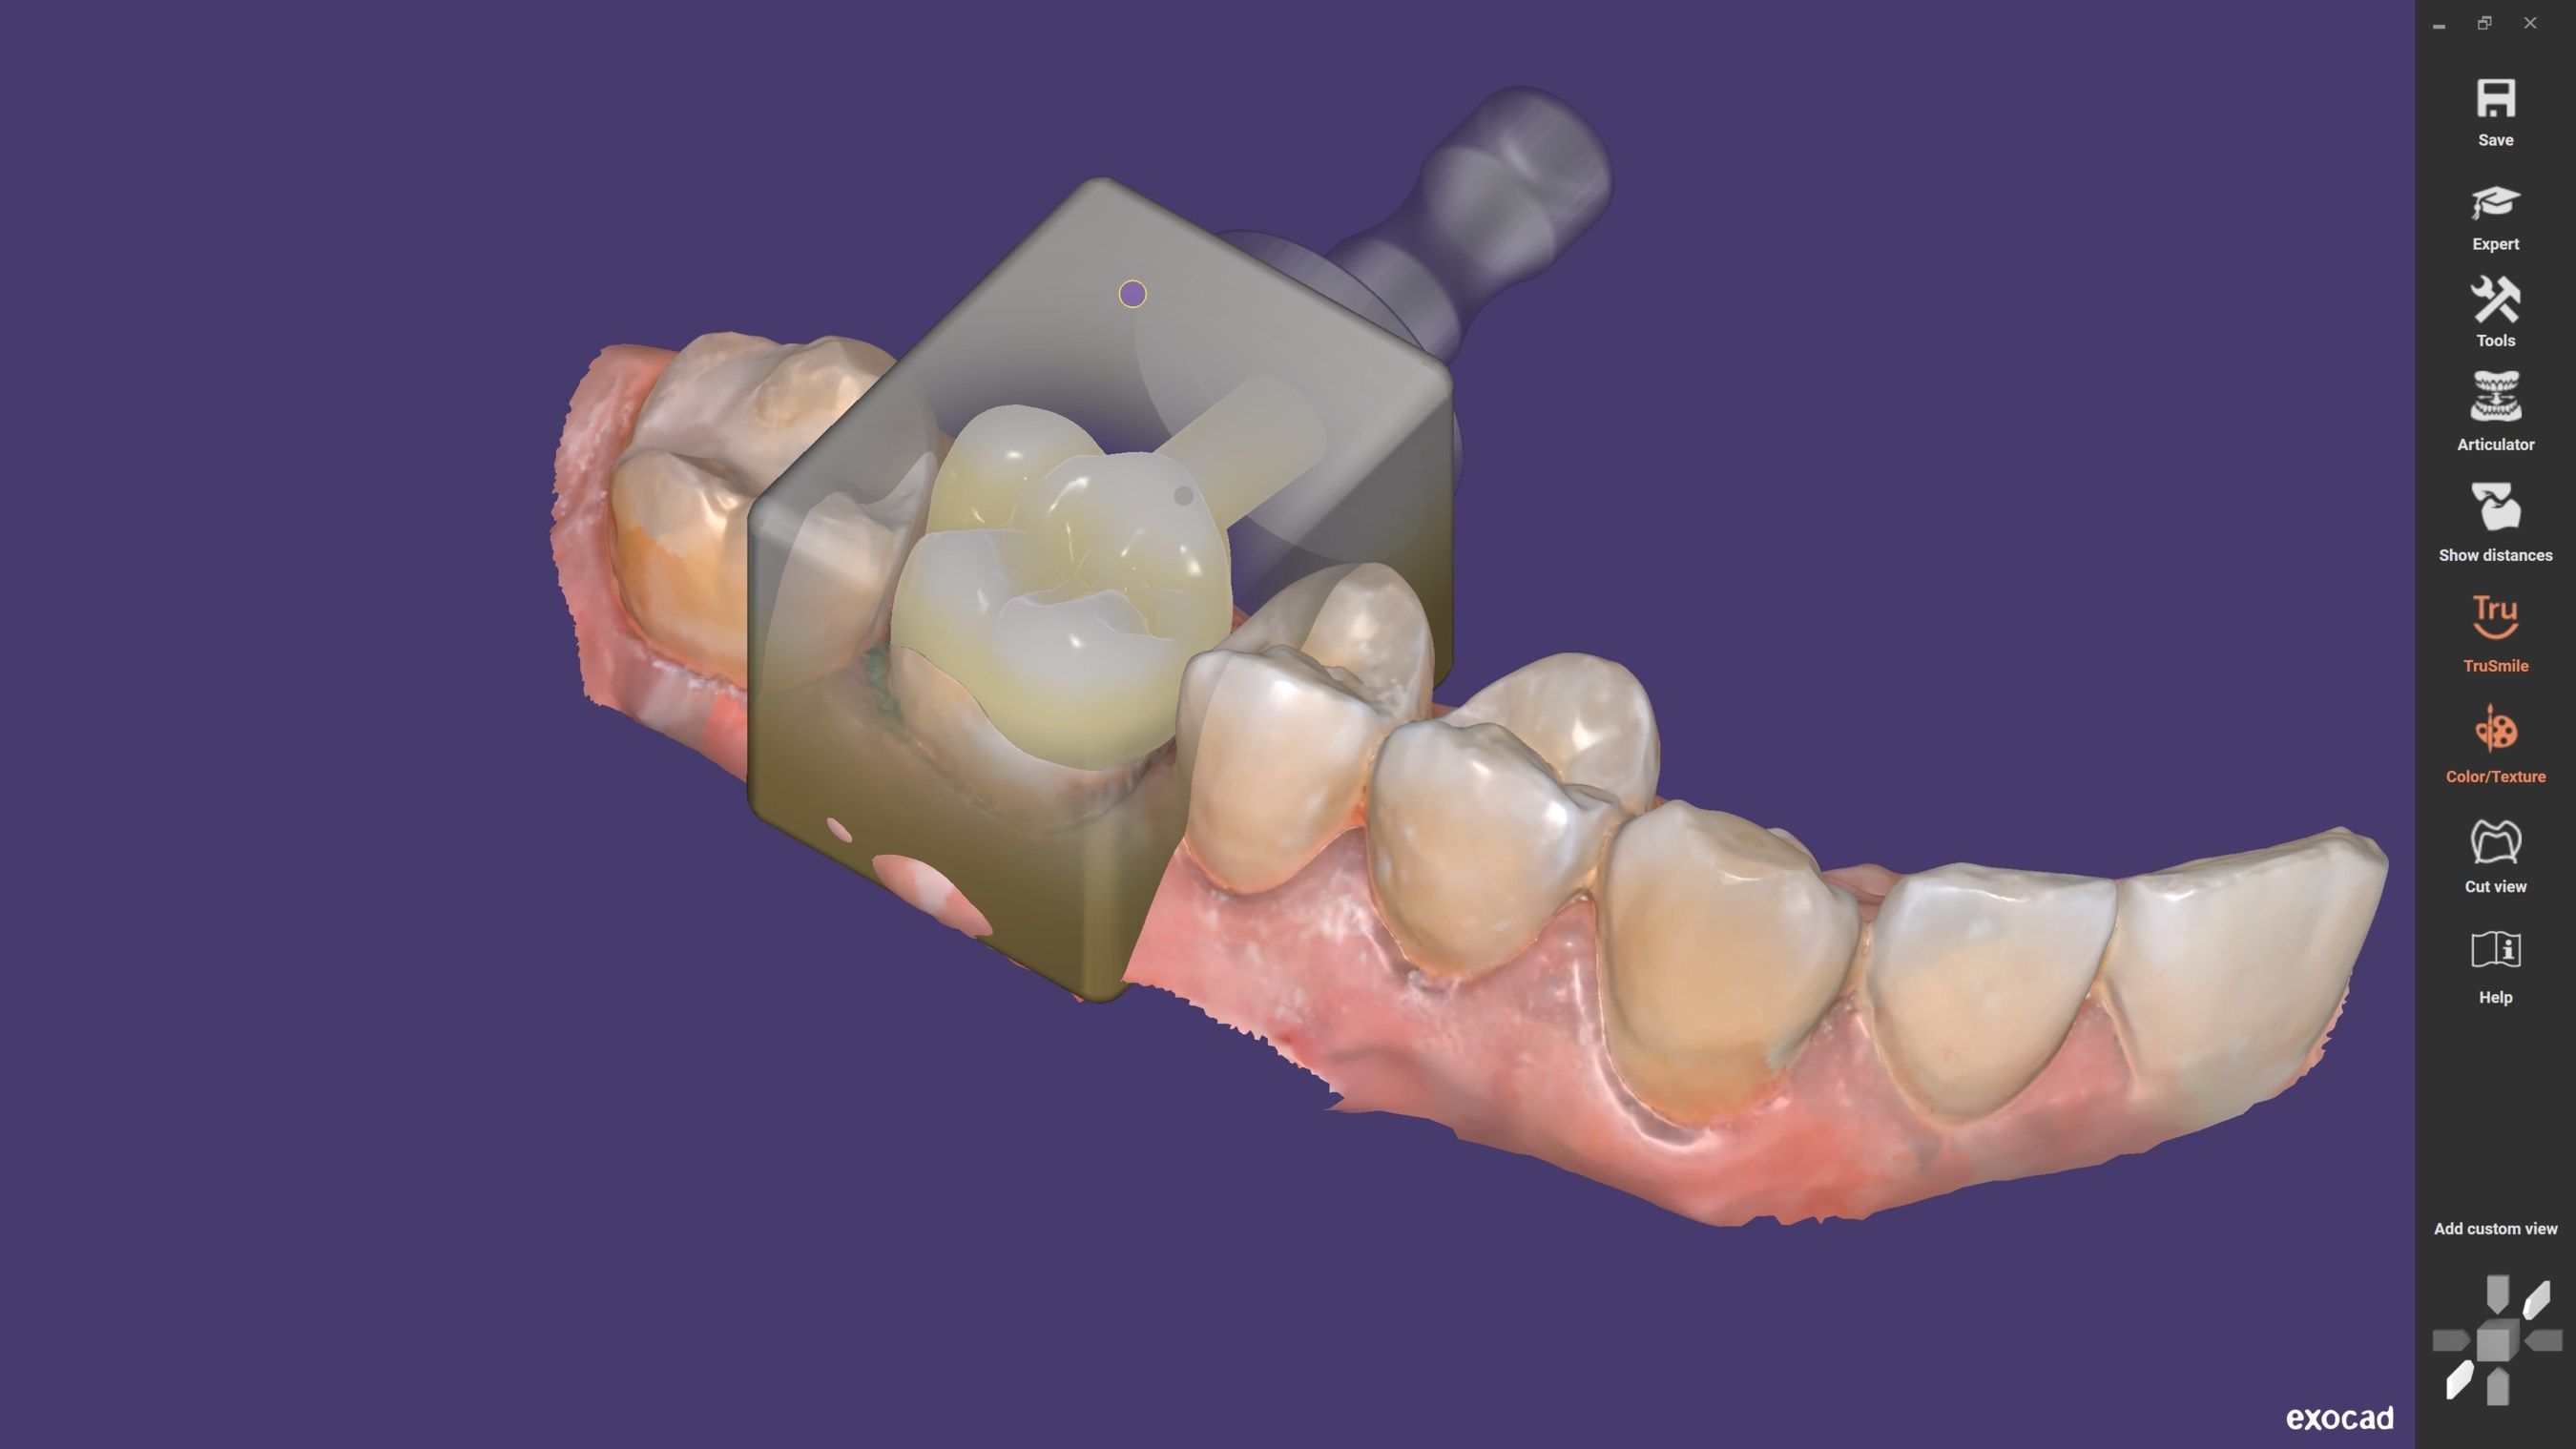

The CS 9600 features breakthrough innovations such as its artificial intelligence (AI)-powered positioning, video cameras, and Live Positioning Assistant to help enable users to produce high-quality images.

“The 5-in-1 CBCT scanner with extraordinary precision.”

"The Swiss Army Knife of diagnostic capabilities.” – Paul Feuerstein, DMD